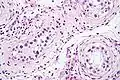

ITGCN. H&E stain.

GCNIS is not palpable, and not visible on macroscopic examination of testicular tissue. Microscopic examination of affected testicular tissue most commonly shows germ cells with enlarged hyperchromatic nuclei with prominent nucleoli and clear cytoplasm. These cells are typically arranged along the basement membrane of the tubule, and mitotic figures are frequently seen. The sertoli cells are pushed toward the lumen by the neoplastic germ cells, and spermatogenesis is almost always absent in the affected tubules. Pagetoid spread of GCNIS into the rete testis is common. Immunostaining with placental alkaline phosphatase (PLAP) highlights GCNIS cell membranes in 95 percent of cases. OCT3/4 is a sensitive and specific nuclear stain of GCNIS.[3]